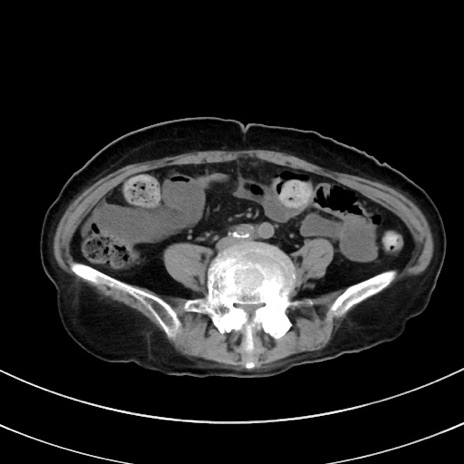

症例33(横断像)

【症例】70歳代 女性

【主訴】心窩部痛

【現病歴】延髄病変の精査・加療にて神経内科入院中。本日より心窩部痛あり。

【既往歴】虫垂炎

【身体所見】右下腹部を中心に圧痛と反跳痛あり。

【データ】WBC 10900、CRP 0.02